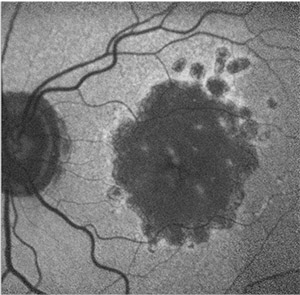

| Figure 5. Fundus autofluorescence of multifocal geographic atrophy presenting as multiple discrete foci of retinal pigment epithelium atrophy, which carries a risk of geographic atrophy progression. Reticular pseudodrusen is also visible (white square). |

Progression rates in eyes with the banded and diffuse FAF pattern were significantly higher compared to eyes without FAF abnormalities or with focal FAF patterns (Figure 4). An additional diffuse trickling pattern exhibited an even greater progression of GA when compared to the other diffuse types.26 Furthermore, the presence of multifocal atrophic spots and extrafoveal lesions were biomarkers predictive of GA progression (Figure 5).27